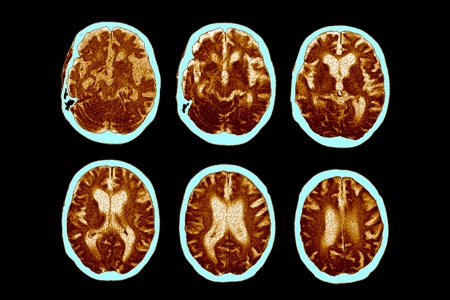

Growth Hormone Injections May Have ‘Seeded’ Alzheimer’s in Some People, Study Suggests

Injections of no-longer-used growth hormone derived from cadavers may have “seeded” Alzheimer’s in some people, small study suggests